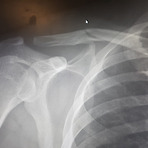

캐나다에서 뼈가 부러졌을 때... 때는 바야흐로 2018년 7월... 8월이던가?? 암튼...이맘때... 저는 태어나서 처음으로 뼈가 부러집니다... 젠장..;; 일단..순간 기억상실증도 걸리고.... 너무 아프고... 정신은 없고... 암튼 그런 상황에서... 급하게 병원으로 왔어요~! 우리 보스와 함께~ 다행히도 저는 MSP가 있었기에 캐나다 의료시설이 100% 무료였답니다. MSP란 BC주에서 사용되는 캐나다 의료보험으로 Medical Service Plan 인가?? 그럴거에요. 캐나다에서 의사한번 보고 오면 약 20만원 이상 깨지기 때문에... 캐나다에서는 의료보험이 필수 필수랍니다. 이게 없다면....여행자 보험도 필수구요~! 어쨋든..전 다행히도 의료보험이 있었기에...무료로 진찰을 받을 수 ..